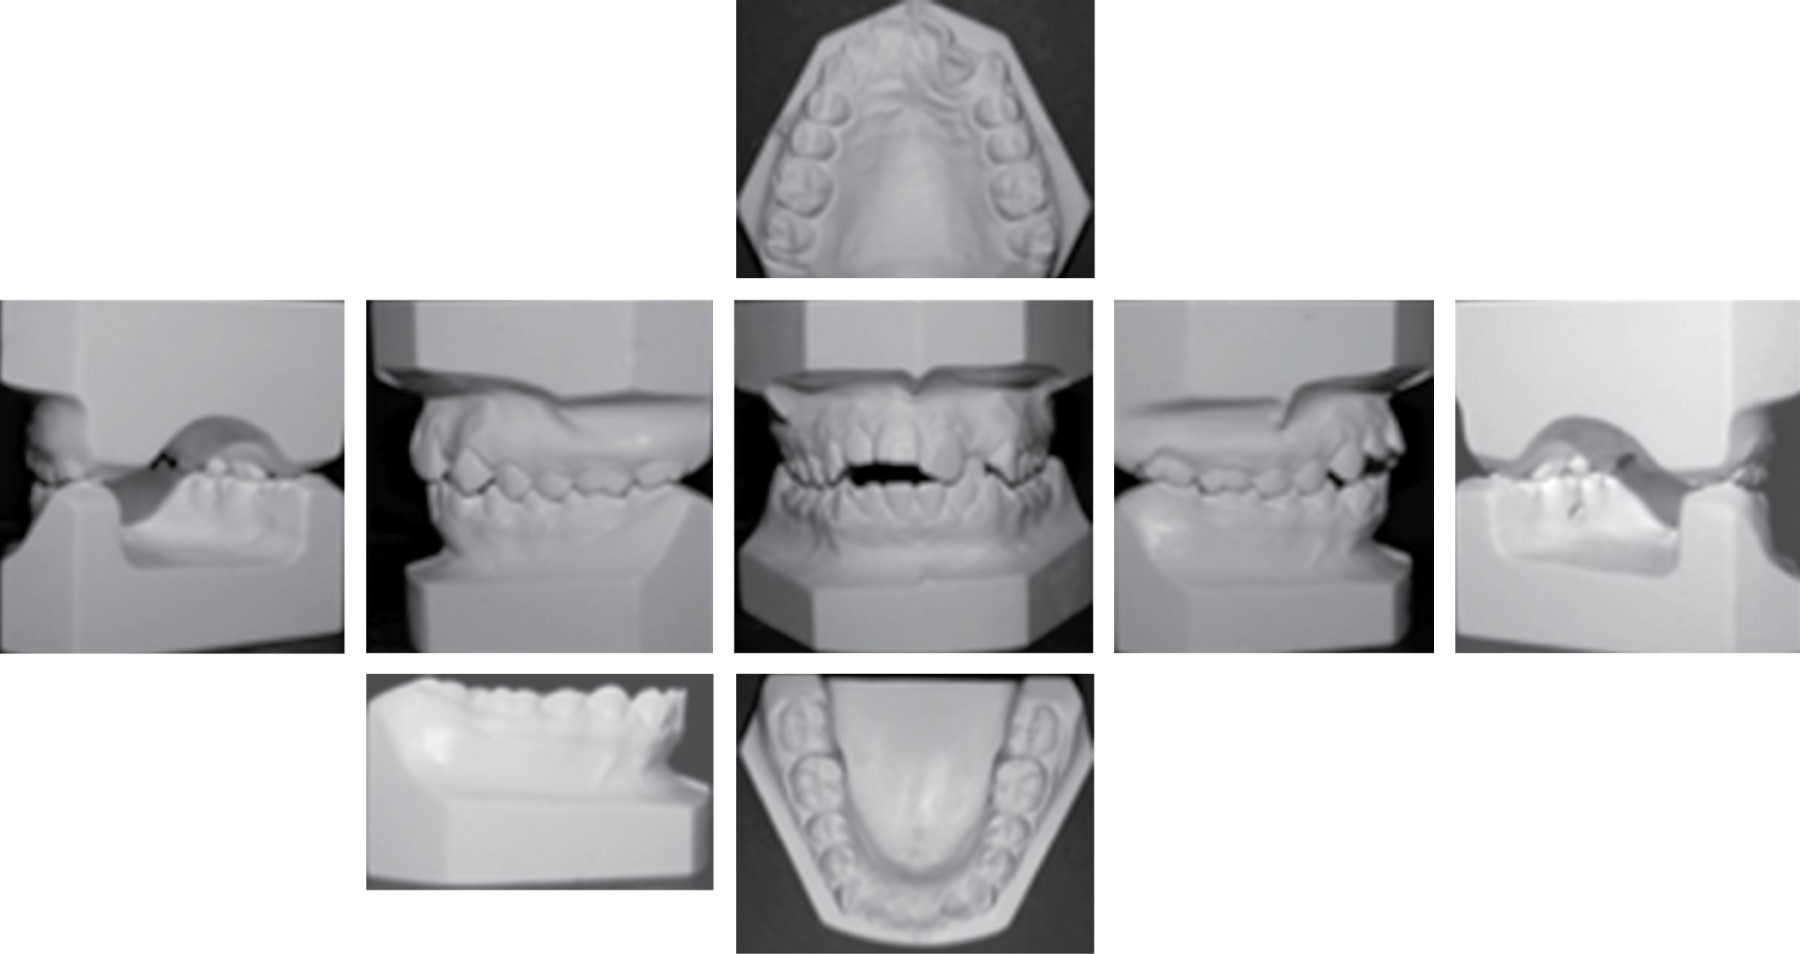

Dentro del análisis intraoral encontramos una mordida abierta anterior más marcada del lado derecho, márgenes gingivales irregulares, líneas medias dentales no coincidentes y la inferior desviada con respecto a la superior 2 mm hacia la derecha, overjet y overbite de -4 y 3 mm, respectivamente, relación clase I molar derecha e izquierda y clase II canina bilateral, arco superior ovalado con apiñamiento severo en el sector anterior, órgano dentario #22 en mordida cruzada, el arco inferior ovalado con apiñamiento leve y una curva de Spee de 1 mm como se muestra en las Figuras 1B y 2.

Figura 2